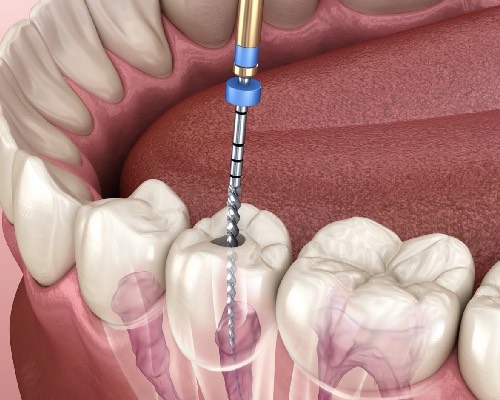

We are Specialised in

We are Specialised in